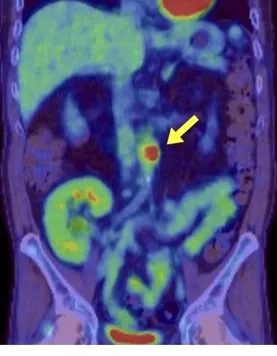

Uma causa incomum de hematúria glomerular intermitente!

Hematúria pós infecção, caso clínicos para auxiliar no entendimento de causas glomerulares comuns e raras...